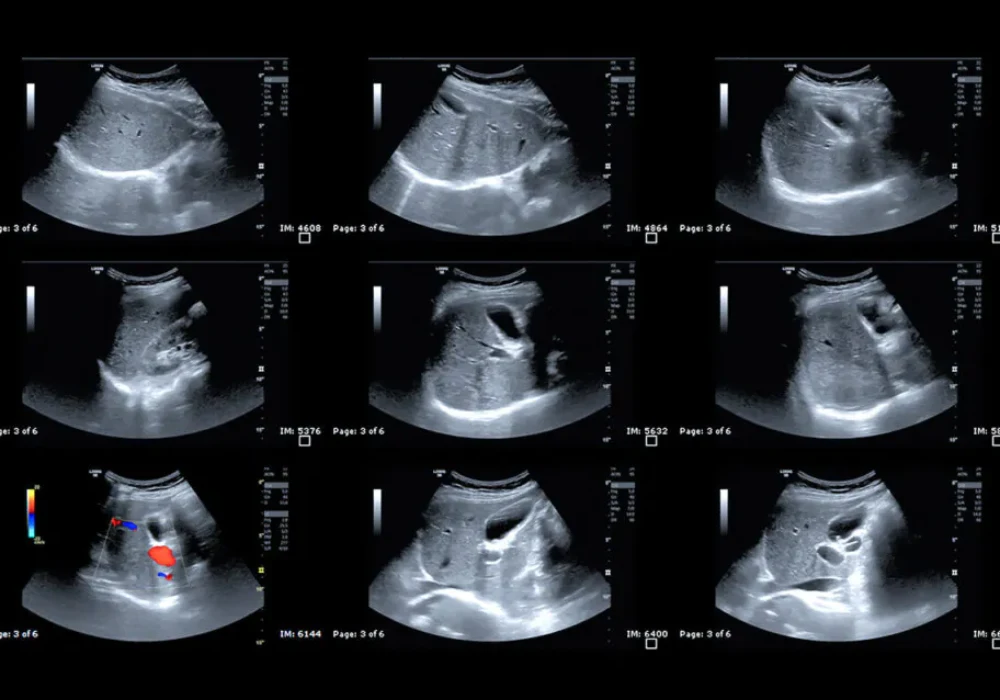

Ultrasound and CEUS images were read independently by two radiologists with more than five years of experience, with a senior radiologist resolving disagreements. Agreement within and between readers ranged from moderate to excellent. To reduce subjectivity, CEUS clips were processed offline using software that calibrated the signal, applied motion compensation and extracted time–intensity curves from regions of interest positioned over the lesion, the immediate margin, surrounding liver and a broader border area. Only curves with adequate fit quality were used. From these curves, the software calculated a suite of perfusion metrics, including average contrast signal intensity known as MeanLin, peak enhancement, wash-in and wash-out areas under the curve, wash-in rate, wash-in perfusion index and wash-out rate.